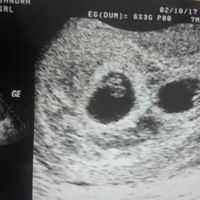

3119 giorni faIn completa paranoia per la paura di non vedere nulla... ansia a mille e poi sbam! eccoli lì, i due semini con cuoricini pulsanti. Emozione unica.Ancora auguri a chi c'è già passata e a chi c'è dentro, e millemila in bocca al lupo a chi ci sta...

3129 giorni faCiao a tutte, questa mattina (5+1) sono stata dal gine che ha voluto farmi la prima eco per verificare l'impianto in utero. E..sorpresa! Di camere ce ne sono 2!una bella sul fondo e l'altra un po' spostata. Sono piccoline (5 mm) ma dice di aver visto...